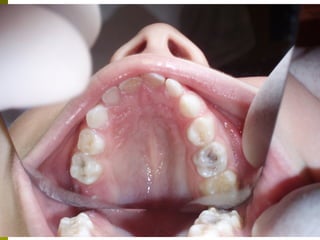

Προληπτικά μέτρα - Καλύψεις οπών και

σχισμών (ΚΟΣ)

 (Προληπτικές εμφράξεις, προστατευτικά, αποφράξεις οπών και

σχισμών, sealants)

   Οι μασητικές επιφάνειες των οπισθίων δοντιών

ευνοούν την κατακράτηση τροφών και μικροβίων και

συχνά τερηδονίζονται αμέσως μετά την ανατολή τους.

 Οι καλύψεις οπών και σχισμών είναι

εύκολες στην τεχνική αλλά και ευαίσθητες.

 Καλή απομόνωση δοντιού, χημική

επεξεργασία (αδροποίηση) και συγκόλληση

ενός ρητινώδους υλικού.

 Ακόμα και αυτή η διαδικασία μπορεί να μην

είναι εφικτή σε κάποια παιδιά